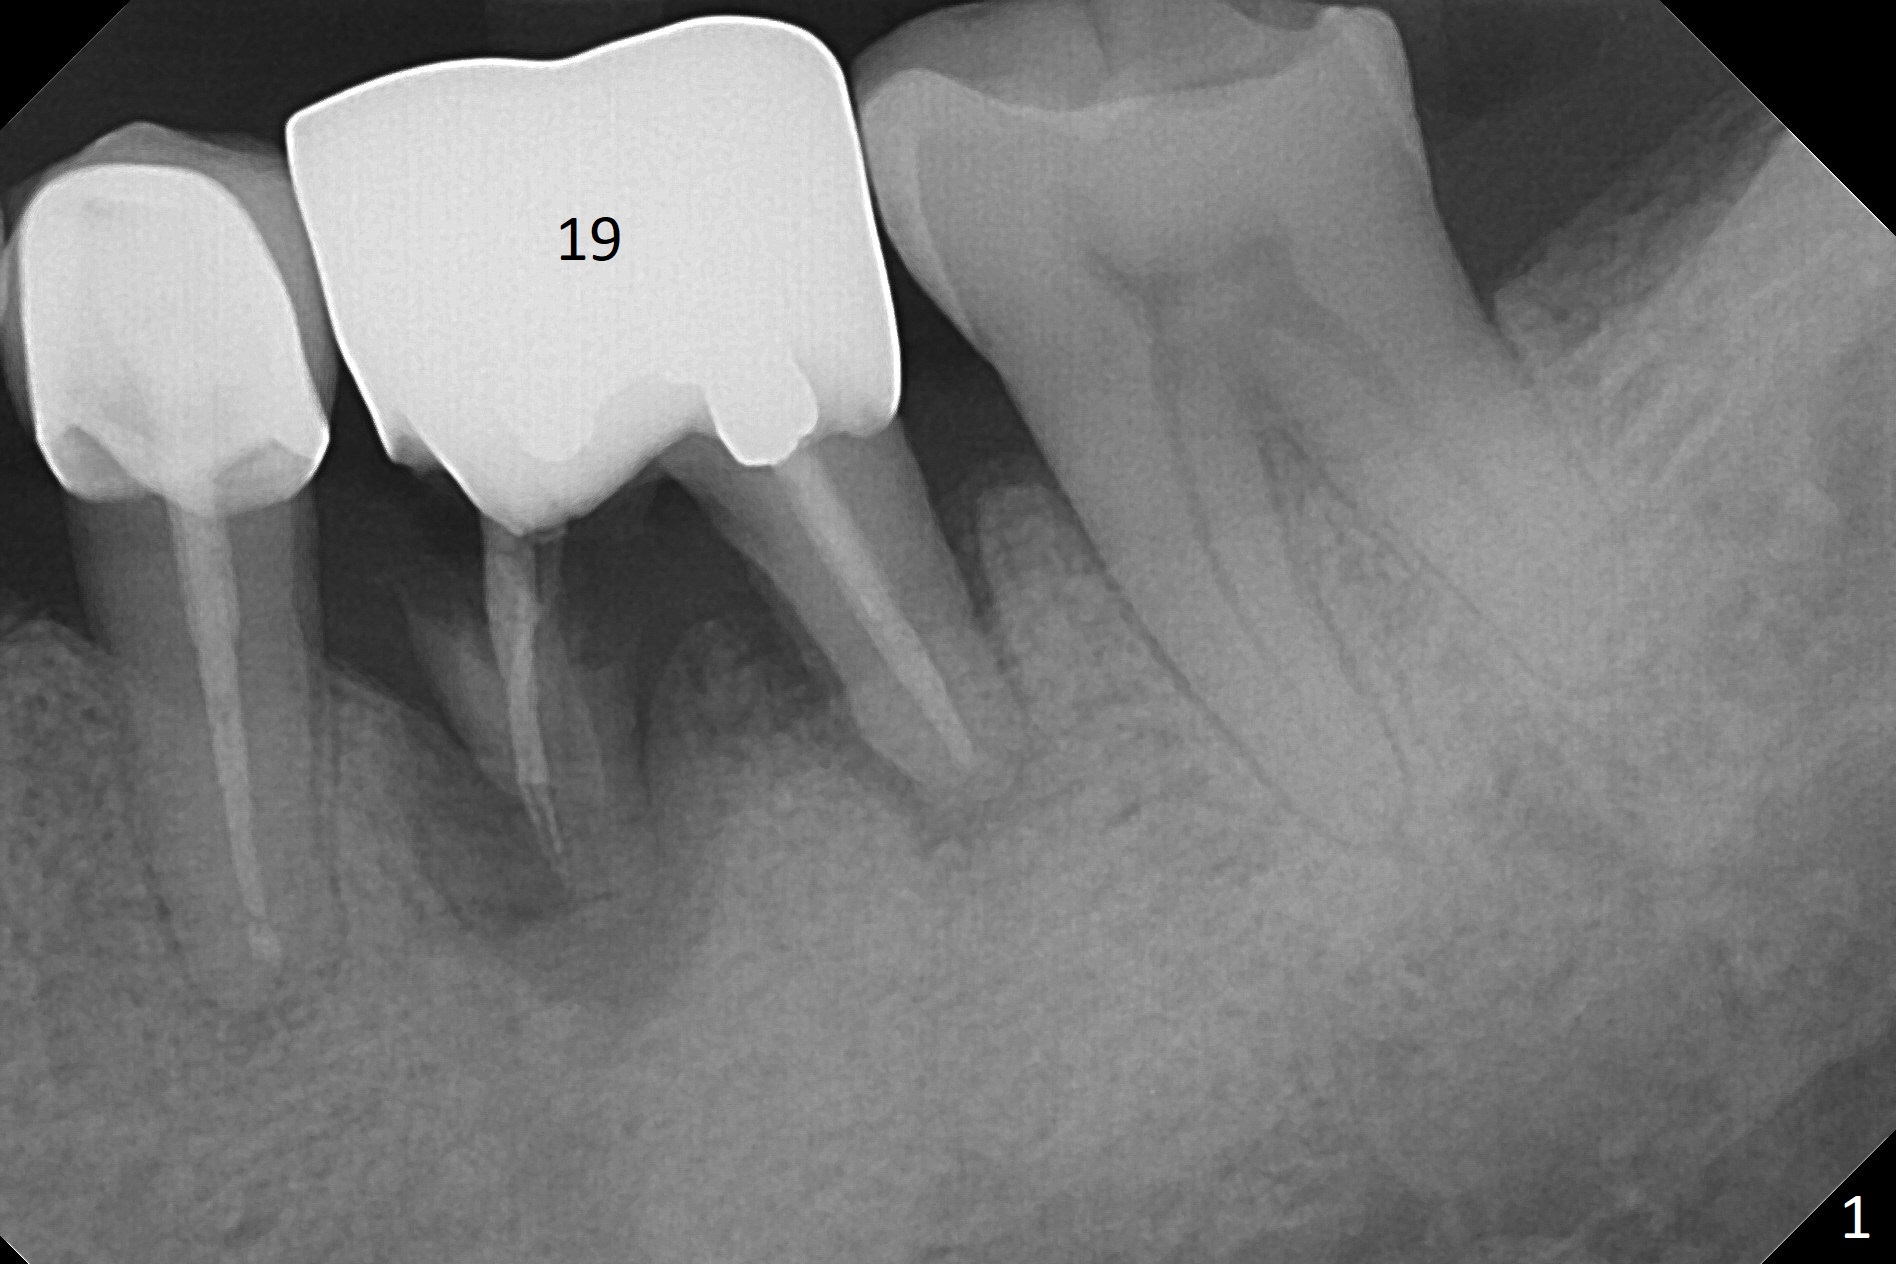

A 64-year-old man will return for #19 extraction and implant. Use IS drills with 10 mm stoppers until 4.5 mm, followed by 5x17 mm tissue-level tap (14 mm gingival level) and PA. Make sure that tap and later implant threads are in the bone or can at least be covered by bone graft (Fig.2,3).